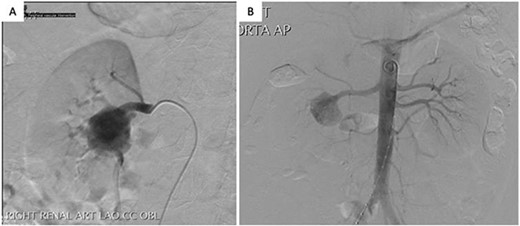

Transperitoneal laparoscopic nephrectomy was performed with the patient in lateral decubitus position. The right kidney was extracted through a Pfannenstiel incision, placed on ice and perfused with Bretschneider’s histidine-tryptophan-ketoglutarate (Custodiol) solution at 4°C. Back-table bench surgery was performed, and the renal artery was carefully dissected to expose a true aneurysm at the hilum, from which five arterial branches arose. Aneurysmorraphy was performed by excising the anterior wall of aneurysm, away from the origins of the branches with primary closure using 6/0 Prolene suture. All five arterial branches were preserved (Fig. 2). A 5 mm vascular dilator was passed through the main renal artery to break the dysplastic web.

Intraoperative photographs of (A) specimen, (B) resected aneurysmal portion, (C) aneurysmectomy and (D) aneurysmorrhaphy/reconstructed renal artery.